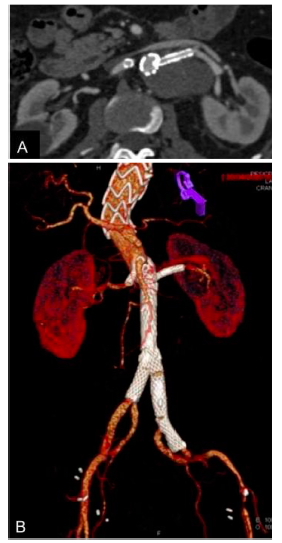

A los 30 días se realizó una angiotomografía de control, que evidenció permeabilidad de ambas arterias renales y de la AMS, ausencia de endoleaks y oclusión completa del LF, de modo que todo el flujo pasaba a través del LV (Fig. 3).